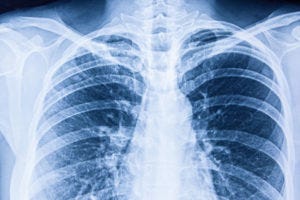

by Zeena Nackerdien PhD, CME Writer, MedPage Today Recent estimates point to a rise in NTM lung disease in the U.S., particularly among those older than 50 or those with chronic underlying lung diseases, such as non-cystic fibrosis bronchiectasis, cystic fibrosis, and emphysema. According to a 1997-2007 estimate of the Medicare population (≥65 years old), NTM lung disease increased at an annual rate of 8.2%. In Annals of the American Thoracic Society, Kevin Winthrop, MD, of Oregon Health and Science University in Portland, and colleagues provided a more comprehensive and contemporary estimate (2008-2015) of the annual incidence and prevalence of NTM lung disease in the U.S. They found that NTM lung disease continued to increase, especially among seniors (≥65 years old) and women. "Our findings add to other recent studies from North America and other regions of the world that show NTM disease is increasing," said Winthrop in a press release. Researchers used Optum Clinformatics Data Mart, a de-identified claims database from a national insurance provider. Individuals with NTM lung disease were defined as those who had at least two medical claims with International Classification of Diseases (ICD) clinical modification codes of ICD-9-CM 031.0 or ICD-10-CM A31.0 dated at least 30 days apart. Over the course of the study period, the annual incidence of NTM lung disease increased from 3.13 (95% CI 2.88-3.40) to 4.73 (95% CI 4.43-5.05) per 100,000 person-years and the annual prevalence rose from 6.78 (95% CI 6.45-7.14) to 11.70 (95% CI 11.26-12.16) per 100,000 persons, meaning that the average annual changes in incidence and prevalence were +5.2% and +7.5%, respectively. Looking specifically at women, the annual NTM lung disease incidence increased from 4.16 (95% CI 3.76-4.60) to 6.69 (95% CI 6.19-7.22) per 100,000 person-years. Correspondingly, the annual prevalence increased from 9.63 (95% CI 9.08-10.22) to 16.78 (95% CI 16.04-17.55) per 100,000 persons. Among seniors, the annual incidence increased from 12.70 (95% CI 11.46-14.07) to 18.37 (95% CI 16.98-19.87) per 100,000 person-years and the annual prevalence increased from 30.27 (95% CI 28.41-32.24) to 47.48 (95% CI 45.37-49.67) per 100,000 persons. Looking at geographic variations, researchers found that the incidence and prevalence of NTM lung disease increased in most U.S. states (incidence increased by at least 10% in 29 states, and prevalence increased by at least 10% in 39 states) and overall at the national level. According to the 2007 American Thoracic Society/Infectious Diseases Society of America guidelines, clinical, radiographic, and microbiological criteria have to be included in the diagnosis of NTM lung disease. Hence, the use of only real-world ICD coding had inherent drawbacks. In addition, intrinsic deficiencies in the diagnostic coding system may, to some degree, have impaired the accurate diagnosis and recording of cases. Because the researchers lacked access to socioeconomic data, they could also not ascertain how these factors might have impacted NTM lung disease incidence and prevalence. Source Reference: Annals of the American Thoracic Society 2019; DOI: 10.1513/AnnalsATS.201804-236OC Study Highlights and Explanation of Findings: Over the course of the study period (2008-2015), the incidence and prevalence of NTM lung disease appeared to be increasing in the U.S., especially among women and people older than 65. "There are likely multiple reasons for these increases," Winthrop said in the press release. "The number of people at risk is increasing because the population is aging and more people are living with chronic lung diseases. Increasing environmental exposure is also likely a factor, as is greater awareness of NTM disease among physicians." He added that the high rates of NTM lung disease among women may be explained by the fact that they live longer and may be more likely to seek medical care. There may also be as yet unidentified biologic and genetic factors that contribute to greater incidence and prevalence among women. Researchers pointed out that the 7.5% increase in prevalence observed from 2008 to 2015 in the current study was comparable to a previously reported 8.2% increase noted in a 1997-2007 analysis of Medicare Part B claims. They ascribed the slight differences between the studies to the difference in identification criteria for NTM lung disease. In addition, age was likely a driver of the higher prevalence of NTM lung disease among Medicare Advantage beneficiaries relative to commercially insured beneficiaries in the current study. Using four healthcare delivery systems combined, another U.S.-based study showed that the average annual age-adjusted period prevalence for 2004 to 2006 was 5.5 cases per 100,000 persons. This result was in keeping with the overall NTM lung disease prevalence rate for 2008 reported in the present study (6.78 cases per 100,000 persons). Previously, an Oregon-based study showed a relatively small increase of 2.2% (P=0.21) in the annual incidence of NTM lung disease from 2007 to 2012 (from 4.8/100,000 person-years to 5.6/100,000 person-years). By comparison, the present study showed an incidence of NTM lung disease in Oregon of 3.01-4.00 per 100,000 person-years in 2008 and 4.51-6.00 per 100,000 person-years in 2015. Study strengths, according to the authors, included the use of a large nationwide, geographically diverse claims database and the use of two diagnostic codes at least 30 days apart to define disease. Reviewed by: Henry A. Solomon, MD, FACP, FACC Clinical Associate Professor, Weill Cornell Medical College